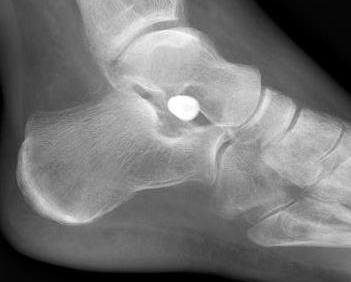

Subtalar arthroeresis

implantimplantimplant

Sinus tarsi implants limit excessive pronation

Endosinotarsal - implant in the sinus tarsi

ArthroArthro

Exosinotarsal - screw external to the sinus tarsi

Smith et al EFORT Open Rev 2021

- 24 articles and 2500 flexible flat feet treated with arthroeresis

- excellent results 80%, poor results 5%

- complications 7%, reoperation rate 3%